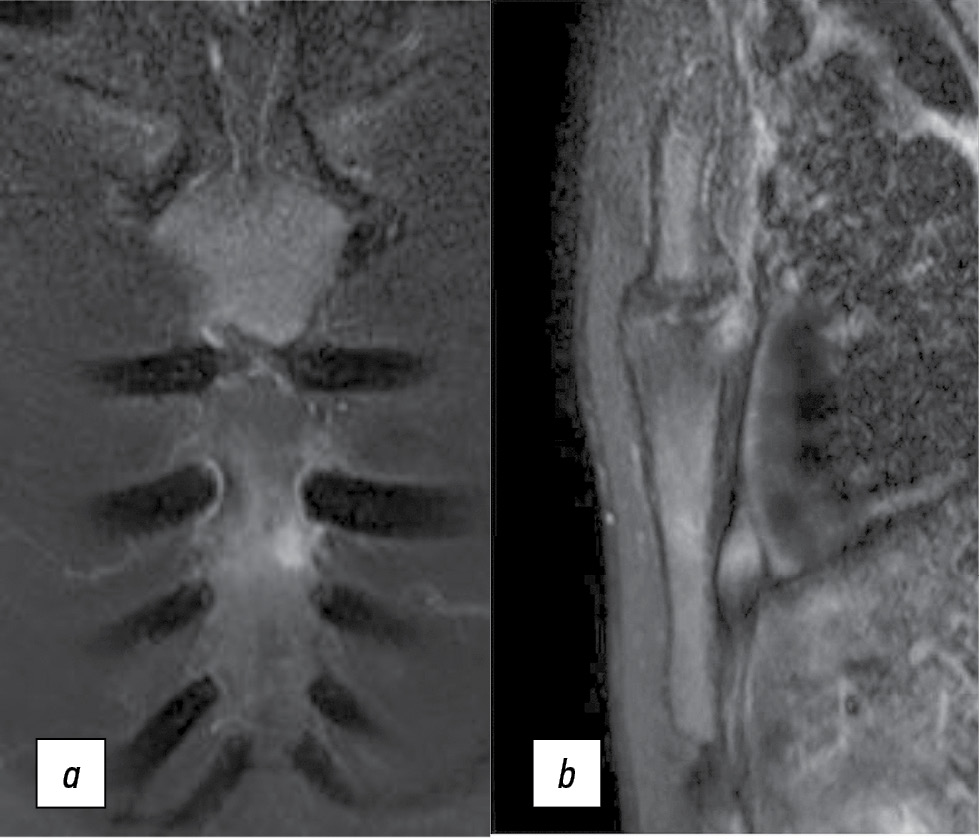

На выполненных 23.03.2021 МРТ до назначения золедроновой кислоты (рис. 2) выявлен выраженный отек правой половины тела грудины с захватом двух ребер.

Рис. 2. Магнитно-резонансная томограмма до назначения золедроновой кислоты. PD/FS, коронарный (a) и сагиттальный (b) срезы.

Fig. 2. Magnetic resonance imaging before use of zolendronic acid. PD/FS, coronal (a) and sagittal (b) partitions.